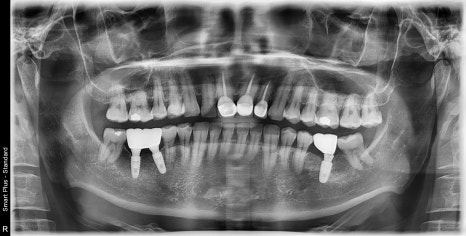

엑스레이에서도 치축이 어긋났고

치아들의 방향이 평행하지 않았습니다.